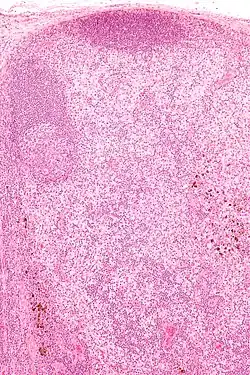

| Micrograph showing dermatopathic lymphadenopathy with the characteristic paracortical histiocytosis and melanin-laden macrophages. H&E stain. | |

Dermatopathic lymphadenopathy is diagnosed by a lymph node biopsy. It has a characteristic pattern of histomorphology and immunohistochemical staining:

- Paracortical histiocytosis

- Melanin-laden macrophages

- Eosinophils

- Plasma cells (medulla of lymph node)